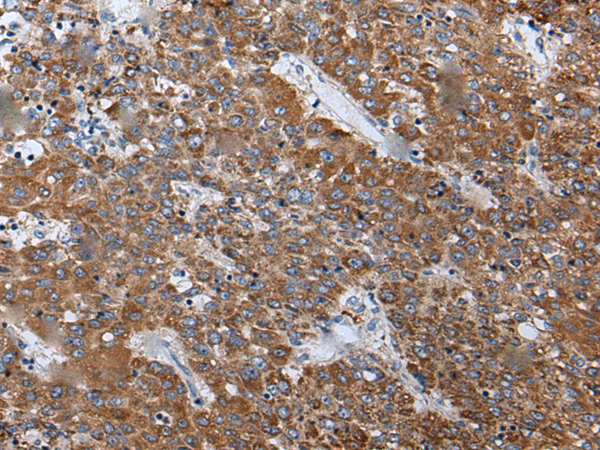

分类: 科研抗体货号: P12879别名: RECQ3; RECQL2; RECQL3应用: IHC反应种属: Human